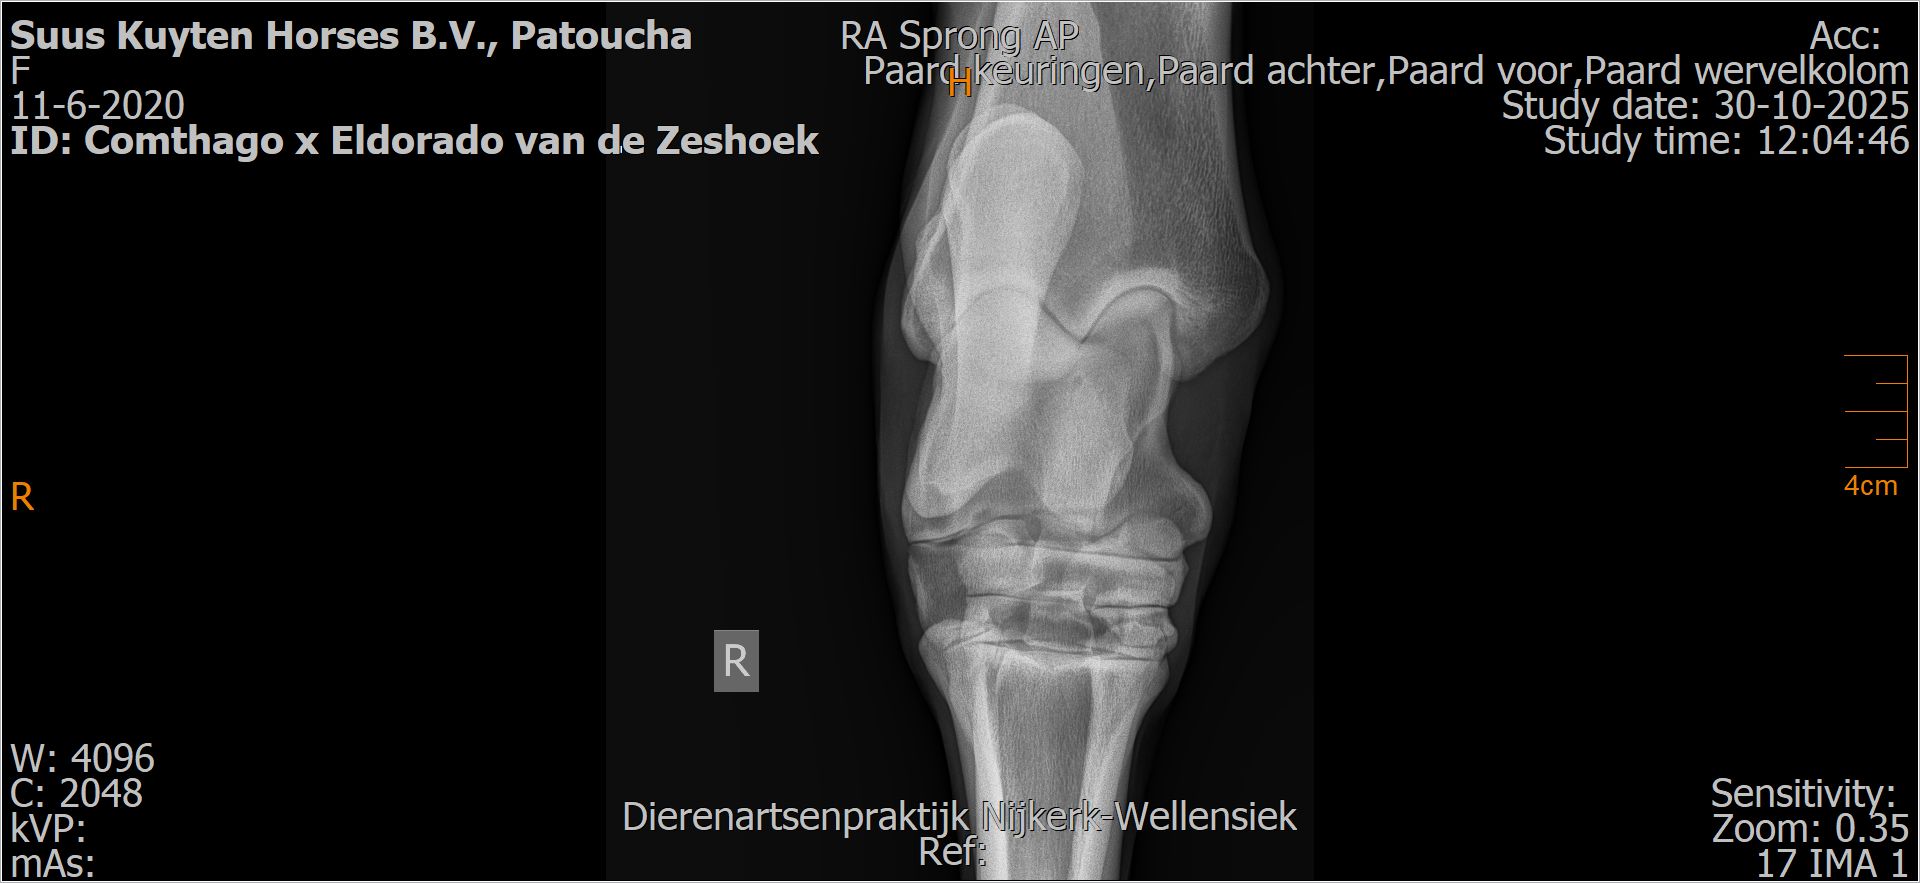

Patoucha

Leeftijd:

7

Röntgenfoto’s